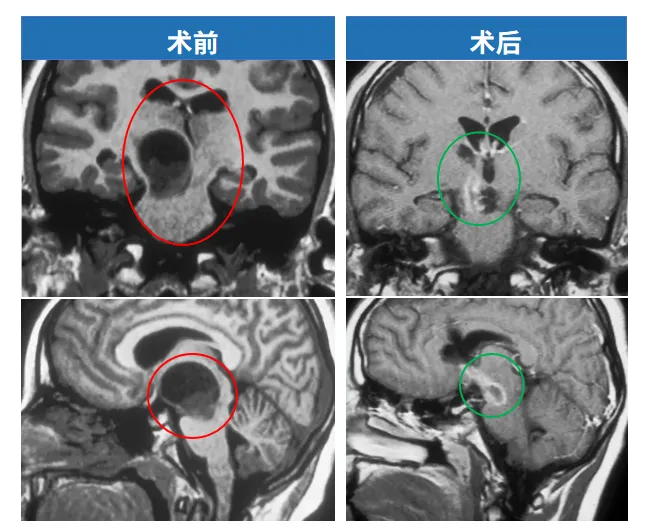

这是一个被医院放弃的孩子。医生说:“位置不好,手术没办法,回家吧。”

最终,肿瘤被完全切除。